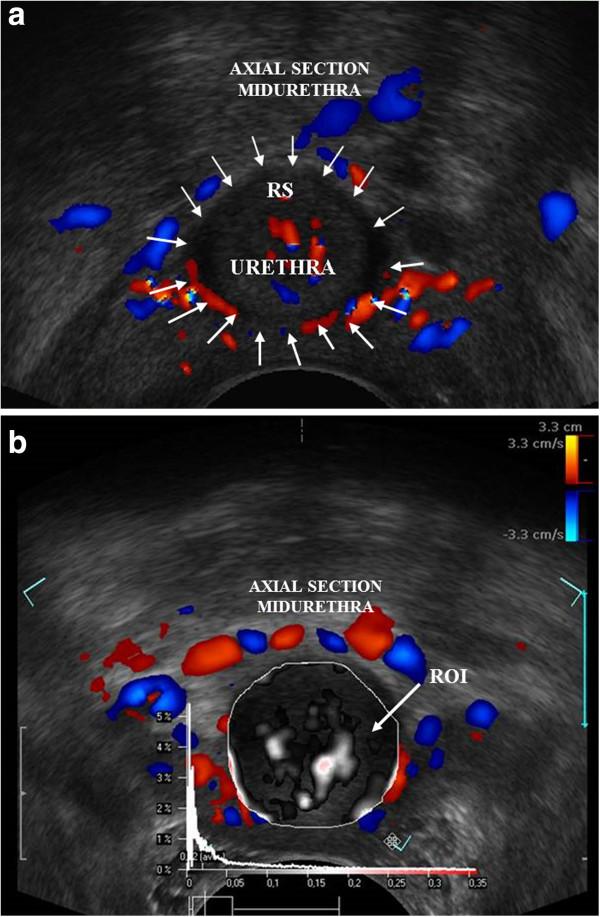

We recruited 61 continent women attending gynaecology clinics between July and October 2009. Exclusion criteria included symptoms of urinary incontinence, voiding dysfunction, pelvic organ prolapse or urinary tract infection. The participants underwent EVUS using high frequency (9-12 MHz) biplane transducer (type 8848 BK Medical), according to a standardised protocol. Colour Doppler US was performed in sagittal plane and in transverse plane at the level of the mid-urethra. Ten seconds video files were recorded and following vascular parameters: flow velocity (Vmix), area of the vessels (Amix), intensity of vascularity (Imix), pulsatility index (PImix) and resistance index (RImix) was evaluated.

There were 30 nulliparous (49.2%) women and 31 multiparous women (50.8%) with a mean (±SD) age of 32 (±4) and 46 (±6) years respectively. Significant impairment of vascularity was observed in multiparous patients as compared to nulliparous and was reflected by increased values of RImix (p < 0.001) and PImix (p < 0.001), and decreased values of Vmix (p < 0.001), Amix (p < 0.001), Imix (p < 0.001) in axial and midsagittal sections of the midurethra. A significant decrease of mean value ± SD of Imix- from 0.02 ± 0.02 in nulliparous to 0.005 ± 0.01 in multiparous was observed. Cronbach alpha, used to assess vascular correlations and parity demonstrated a reduction when expressed only for vascular parameters, indicating that number of deliveries is an important factor while assessing urethral vascularity.